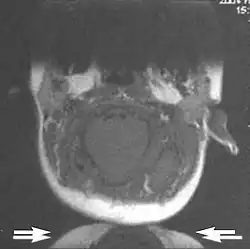

Metal artifacts occur at interfaces of tissues with different magnetic susceptibilities, which cause local magnetic fields to distort the external magnetic field. This distortion changes the precession frequency in the tissue leading to spatial mismapping of information. The degree of distortion depends on the type of metal (stainless steel having a greater distorting effect than titanium alloy), the type of interface (most striking effect at soft tissue-metal interfaces), pulse sequence and imaging parameters. Metal artifacts are caused by external ferromagnetics such as cobalt containing make-up, internal ferromagnetics such as surgical clips, spinal hardware and other orthopaedic devices, and in some cases, metallic objects swallowed by people with pica.[3] Manifestation of these artifacts is variable, including total signal loss, peripheral high signal and image distortion (Figs 3 and 4).[1] Reduction of these artifacts can be attempted by orientating the long axis of an implant or device parallel to the long axis of the external magnetic field, possible with mobile extremity imaging and an open magnet. Further methods used are choosing the appropriate frequency encoding direction, since metal artifacts are most pronounced in this direction, using smaller voxel sizes, fast imaging sequences, increased readout bandwidth and avoiding gradient-echo imaging when metal is present. A technique called MARS (metal artifact reduction sequence) applies an additional gradient, along the slice select gradient at the time the frequency encoding gradient is applied.